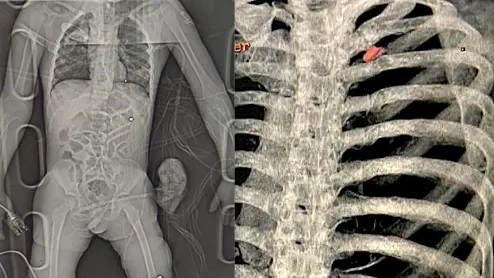

Radiology imaging of two wounded civilians with bullet and shrapnel embedded in tissue. Left is a digital X-ray of a patient with shrapnel in the chest and a bullet in the leg who was brought to the National Children's Specialized Hospital in Kyiv. Right, a 3D CT scan reconstruction of a bullet in the chest of a 40-year-old father who as attempting to evaculate his wife and child from the Russian advance near Kyiv when the Russians opened fire on him. Image from the Ukraine Heart Institute in Kyiv.

Many radiologists stepped up to do their part for the war effort by staying at their hospital posts and helping the wounded as they started coming in.